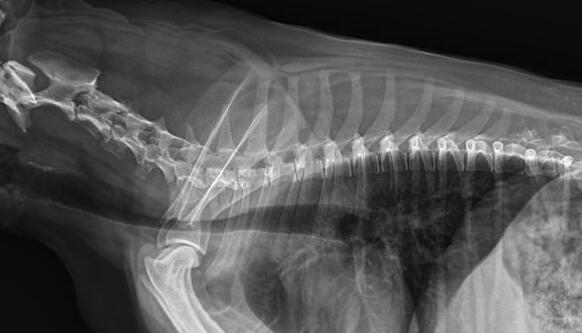

利用宠物dr拍摄图像效果图

1、DR的DQE检测效率可达74%,而传统普通胶片组合X线照片DQE为30%。

2、宠物DR成像速度快,采集时间10ms以下,成像时间仅为3秒,对于受伤的宠物来说,检查越快速,越能早点帮助其治疗,降低痛疼。对于宠物主人而言,也是一种心理安慰。

3、数字图像可进行后处理。图像后处理是数字图像的很大特点。只后要保留原始数据,就可以根据诊断需要,并通过软件功能,有针对性的对图像进行处理,以提高诊断率。

4、兽用dr所具备的辐射剂量较低,相比传统的ct而言,对于宠物和医生而言,都是一种?;ぁ?br /> 5、有效解决了图像的存档管理与传输,采用光盘刻录形式保存图像资料,随时能为受检者提供照片打印服务,这样大大提高了工作效率。对于接诊量比较大的宠物医院来说,这个具备大的优势。